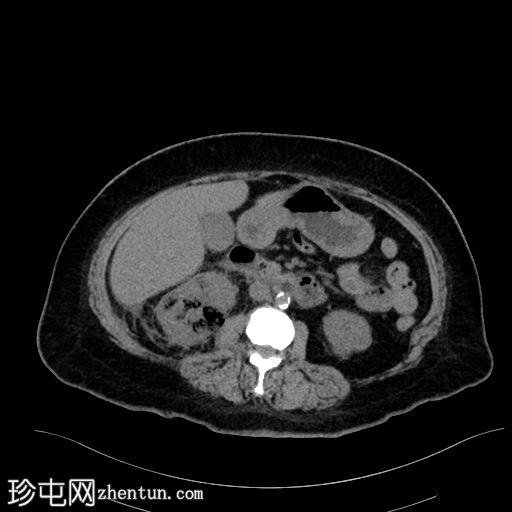

矢状位

平扫

肾实质内可见多个气体囊,主要累及右肾中部和下极。

肾周脂肪组织中度炎症性改变,并可见条索状肾周积液。

气体未延伸至肾盂或输尿管。

无肾积水。

少量微小的非梗阻性肾结石(砂砾)。